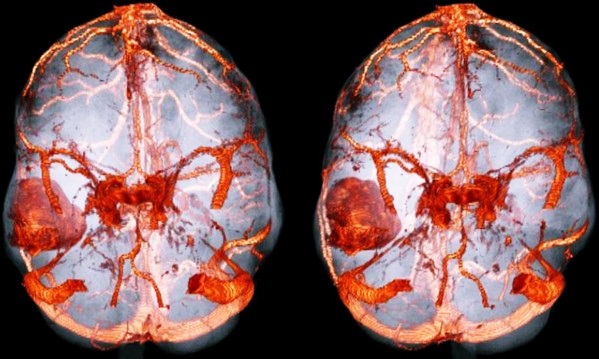

Сложна диагностика заболевания у маленьких детей. У новорожденного ребенка непросто дифференцировать симптомы, поэтому в таких случаях адекватное лечение начинается только после специфической диагностики (КТ, МРТ и т.д.).

- Магнитно-резонансная томография. С помощью МРТ достаточно быстро устанавливается точное расположение воспалительного очага в мозге человека.